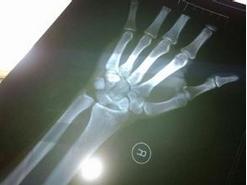

1.摔倒时尽量不要用手掌去撑地,这是最关键的,因为这样容易造成骨折。

4.当然如果你是向前摔出去,这时是可以用手撑地的,但是要是前扑的姿势,类似于青蛙,双脚着地后才能用手去称地保持平衡,记住是手指撑地而不是手掌。